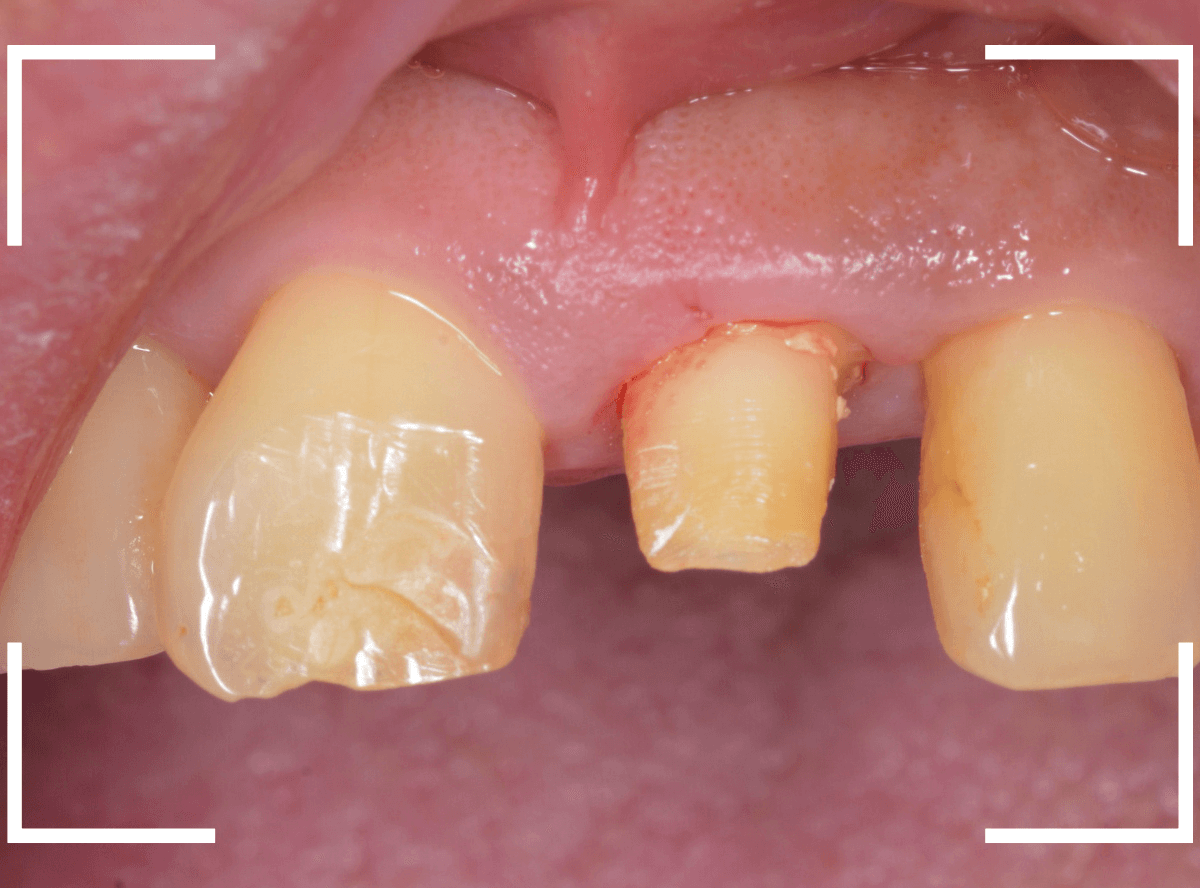

さし歯を被せるために、歯の土台をたてて、歯を削ります。

歯の高さが低く、このままさし歯を作っても、すぐに取れてしまう事が予想されます。

隣りの歯と比べても歯肉の際が浅いため、若干歯肉を切開して、歯の高さを稼ぎます。

歯肉を切開した部分に、仮歯のレジンを盛って確認します。

大体、隣の歯の高さと合わせる事が出来ました。